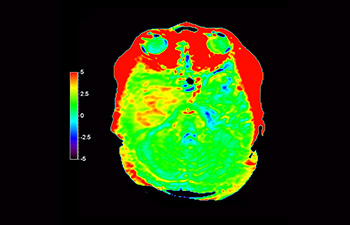

En una sociedad con una alta incidencia de trastornos neurológicos, Philips se compromete a ofrecer una excelente asistencia en el tratamiento y claridad en el diagnóstico para todos los pacientes. Hoy en día, aunque la RM es la modalidad de referencia para la adquisición de imágenes de neurooncología, su precisión a la hora de clasificar los tumores y de evaluar el seguimiento de los tratamientos aún tiene mucho margen de mejora. 3D APT (Amide Proton Transfer, transferencia de protones de amidas) es un exclusivo método de adquisición de imágenes por RM cerebral sin contraste que tiene por objetivo ofrecer un diagnóstico de neurooncología más fiable. 3D APT utiliza la presencia de proteínas celulares endógenas para producir una señal de RM que se corresponde directamente con la proliferación celular, que es un marcador de la actividad tumoral. 3D APT puede ayudar a los profesionales de la salud debidamente instruidos a diferenciar los gliomas de baja malignidad de los gliomas más graves, así como a diferenciar la progresión tumoral del efecto del tratamiento1.

con 3D APT